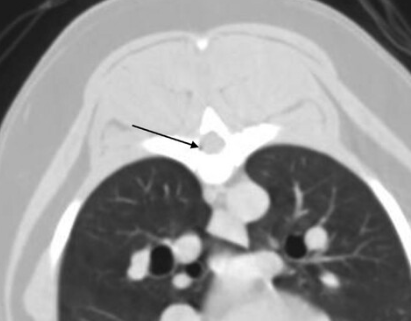

CT 촬영을 하다 보면 실제 공기방울이 심심치 않게 발견된다. 모두 의학적 이유로 발생한 것일까? 에 대한 궁금증을 풀어줄 논문이 나와 소개한다.

물론 다량의 공기가 혈관으로 주입된다면 문제가 발생할 수 있을 것이다. 하지만 소량의 공기는 흔하게 발생하는 현상이고 이를 모두 문제라고 말할 수 없다.